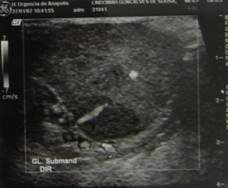

Ao ultrapassar os planos anatômicos em direção à glândula, foi feita uma cuidadosa separação da mesma em relação aos tecidos vizinhos. (FIGURA 6) (FIGURA 7)

clip_image015[5]

Pinça hemostática demonstrando a relação superior do linfonodo submandibular